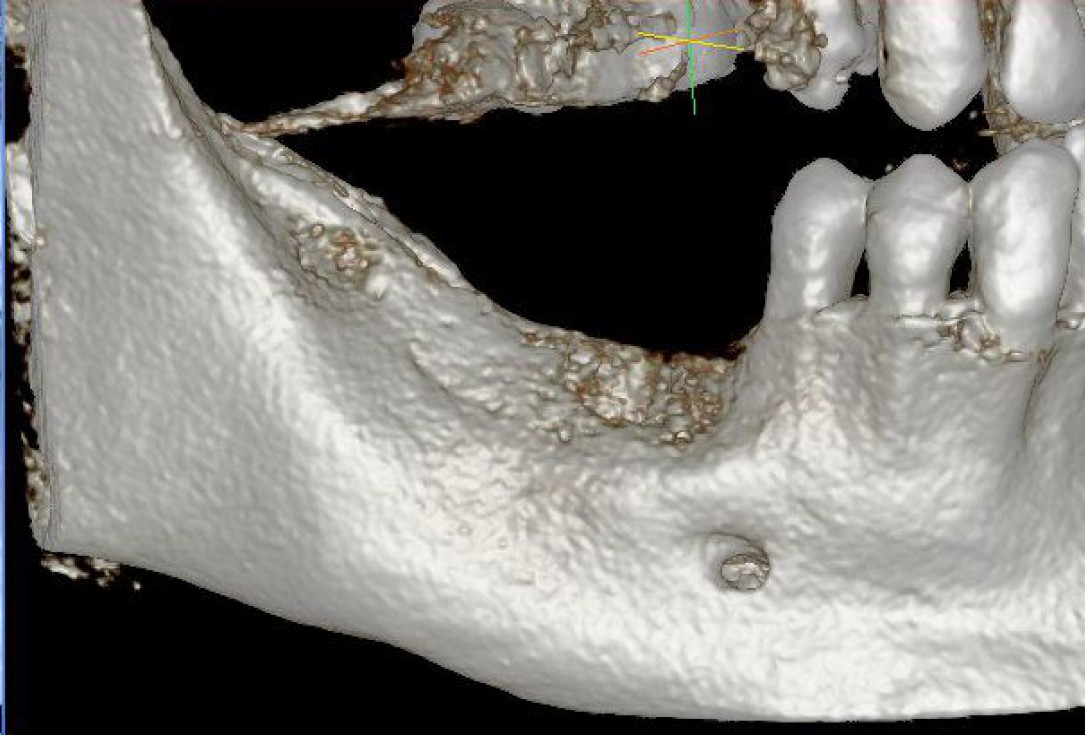

01/28 - Model of the initial defect computed from a CBCT scan - buccal viewThree-dimensional augmentation with maxgraft® cortico - Dr. R. Würdinger